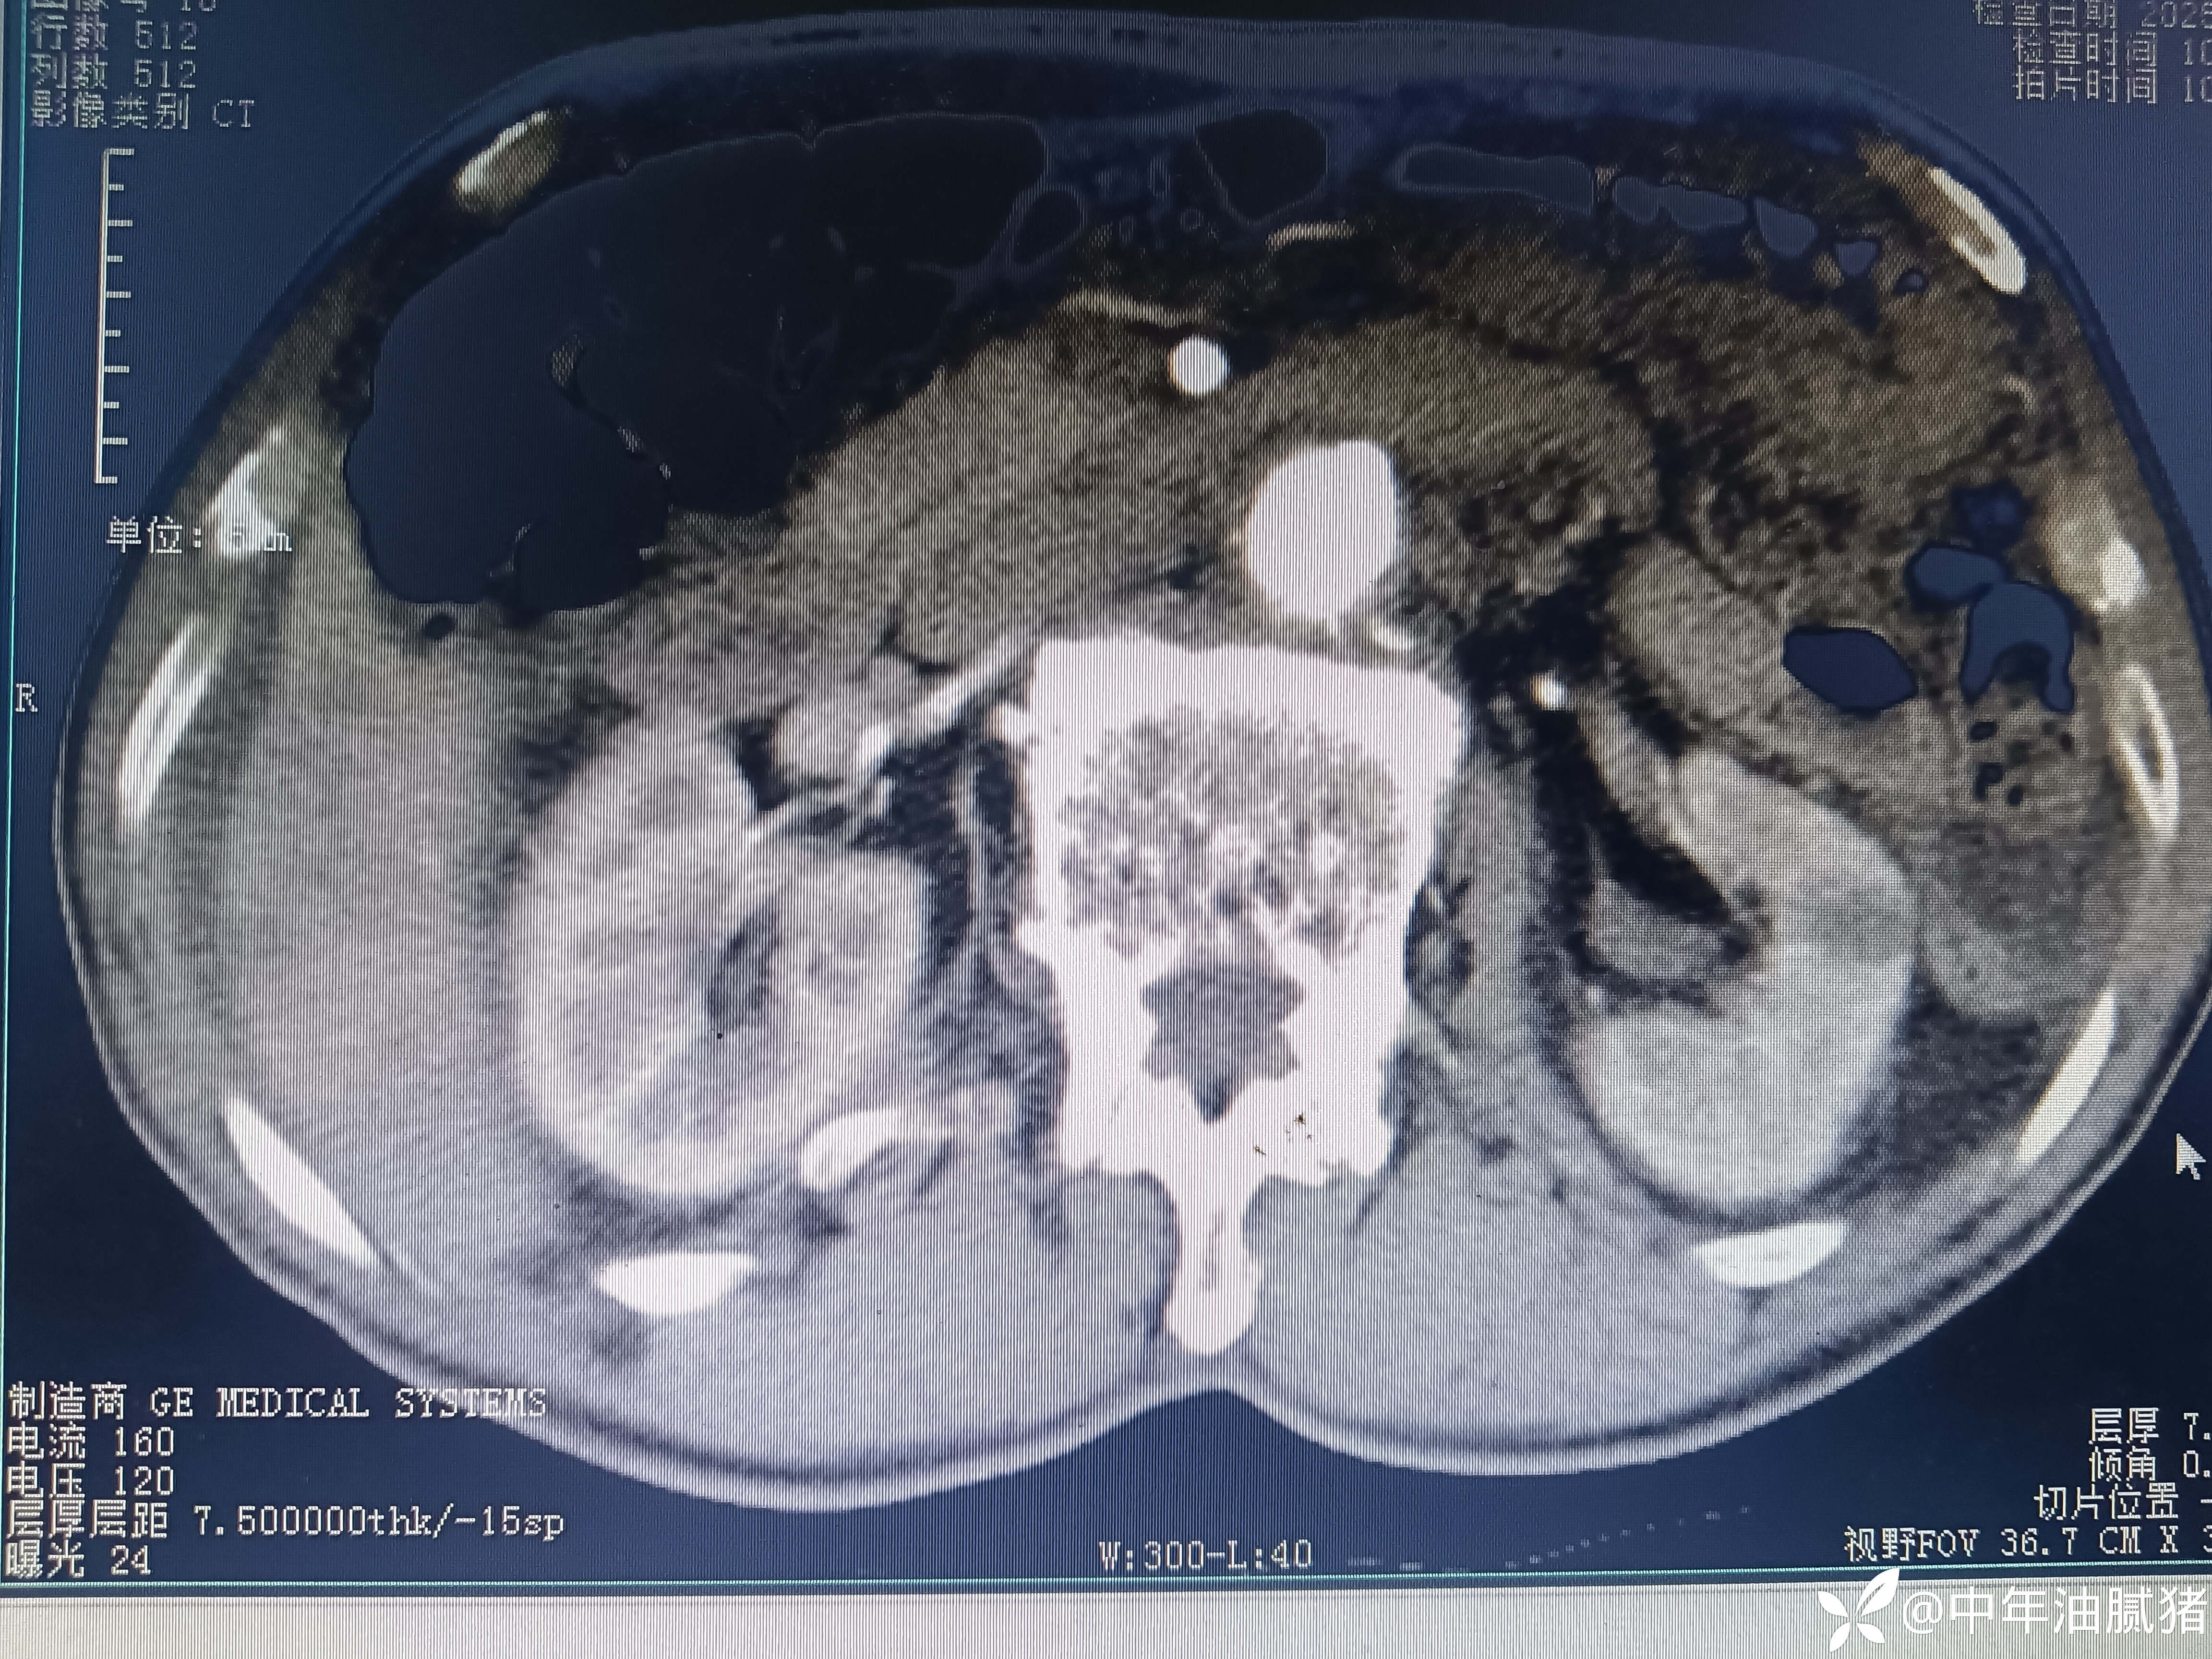

肺ct看到肝内病灶,行增强检查

建议增强ct.报告如下

看后,我隐隐约约觉的不是肝囊肿那么简单?元芳,你怎么看?狄阁老,我也是这么认为!摇人,掏起手机:喂,w主任,请帮我看看这个ct。5分钟后报告修改如下